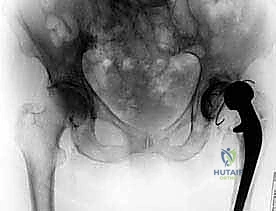

* التصوير الشعاعي: الأشعة السينية (X-rays) لملاحظة أي تخلخل في المفصل أو تآكل في العظام. في حالات معقدة، قد يتم استخدام الأشعة المقطعية (CT scan) أو الرنين المغناطيسي (MRI) المتوافق مع المعادن.

- الاستخراج المعقد (Implant Removal): يتم فتح المفصل بحذر شديد لحماية الأنسجة المتبقية. يقوم الدكتور هطيف باستخدام أدوات جراحية دقيقة ومتخصصة لإزالة المفصل الصناعي القديم (الساق المعدنية، الكوب الحُقي، والمسامير). التحدي هنا هو إزالة هذه الأجزاء دون التسبب في كسور إضافية للعظم الذي قد يكون هشاً بسبب العدوى.

بمجرد التأكد من خلو الجسم من العدوى، يعود المريض لغرفة العمليات لإجراء الجراحة النهائية.

- إعادة بناء العظم (Bone Grafting): في كثير من الحالات، تكون العدوى قد دمرت أجزاء من عظام الحوض أو الفخذ. هنا تتجلى خبرة الدكتور هطيف في استخدام طعوم عظمية (إما من بنك العظام أو عظام صناعية) أو استخدام دعامات معدنية متقدمة (Augments و Cages) لتعويض العظم المفقود وبناء أساس قوي للمفصل الجديد.

- زراعة مفصل المراجعة المعقد (Revision Arthroplasty): المفاصل المستخدمة في هذه المرحلة تختلف عن المفاصل الأولية؛ فهي مصممة لتكون أطول، وأكثر استقراراً، وتحتوي على آليات تثبيت معقدة لتعويض ضعف العضلات والأربطة. يتم تثبيت الكوب الحُقي الجديد وساق الفخذ بدقة ميكانيكية حيوية فائقة لضمان عدم تعرض المريض للخلع مستقبلاً.